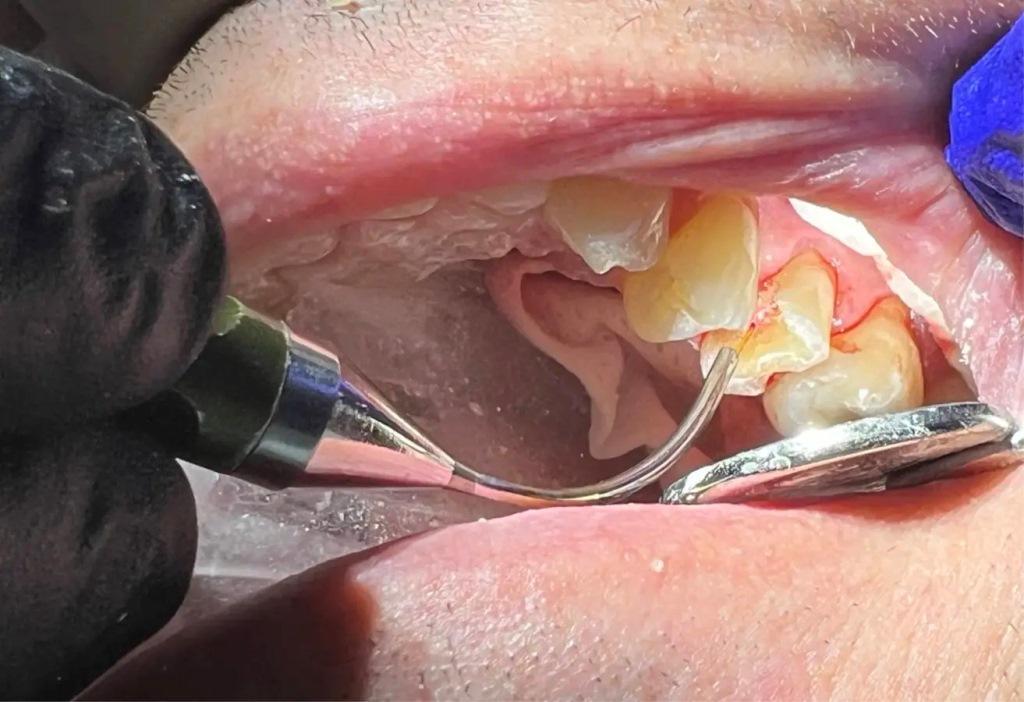

Сразу после контакта с пульпой, использовался Nd:YAG-лазер в режиме абляции (4,6 Вт, 100 мкс, 230 МДж, 20 Гц) на область воздействия при 50-75 Дж, чтобы остановить кровотечение и закрыть область воздействия, не проникая в пульпарную камеру более чем на 3 мм (фото 6). Затем на тех же настройках лазер использовался с мощностью 162 Дж для стерилизации окружающих структур зуба и биостимуляции для активации стволовых клеток, повышения репаративной активности дентина и снижения уровня простагландинов в послеоперационном периоде. Когда обработанный участок зуба был стерильным, перед нанесением покрытия на дентин и пульпу были приняты меры по предотвращению загрязнения. Сразу использовали небольшое количество стеклоиономерного цемента GC FujiCEM (GC America, фото 7). Затем была выполнена реконструкция культи зуба с использованием смолы RelyX Unicem (3M ESPE) на окружающих здоровых участках зуба для обеспечения хорошего сцепления между материалом культи и дентином. Подготовка коронки была завершена (фото 8). С помощью сканера TRIOS (3Shape) был снят цифровой слепок, изготовлена временная коронка и зацементирована с помощью цинкоксидэвгенольного цемента IRM (Dentsply Sirona). Окончательная коронка была установлена и закреплена через две недели, пациент сообщил об отсутствии чувствительности, так как лечение проводилось при воздействии пульпы.

Фото 6: Обработка пульпы с помощью Nd:YAG-лазера для устранения любых бактерий, которые могли привести к инфицированию пульпы и потребовали бы эндодонтического лечения.